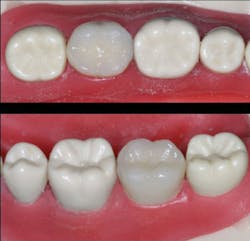

Finish and polish the new resin crown, and seat it with a resin-modified glass ionomer cement

When finishing, be very careful to leave the margins intact. This is the final crown for the patient (figure 6)!

Figure 6: The finished and polished resin crown has been cemented with resin-modified glass ionomer cement to take advantage of the cariostatic characteristics of that cement-in this case, the popular 3M RelyX Luting Plus was used.